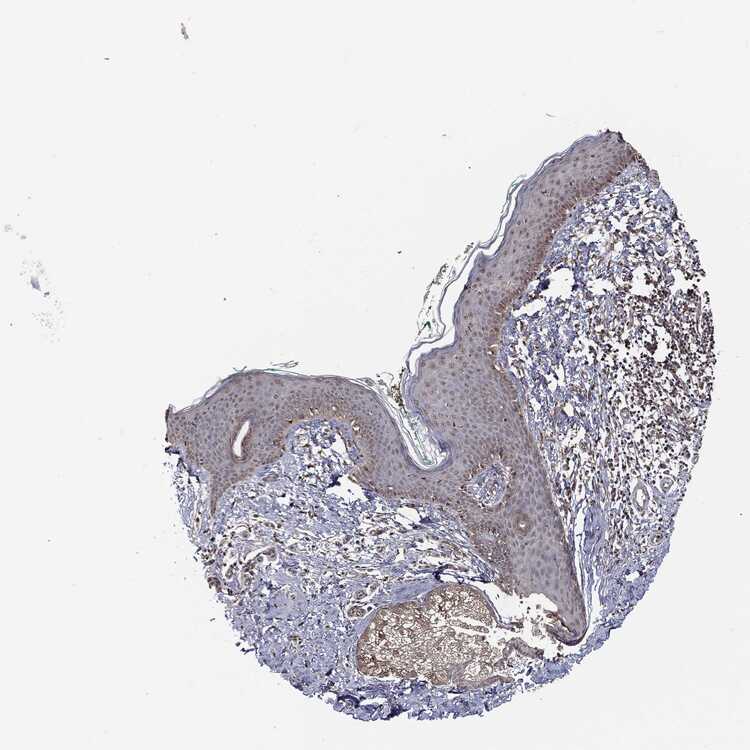

SKIN 2 - Antibody stainingi

Antibody staining in the annotated cell types in the current human tissue is reported as not detected, low, medium, or high, based on conventional immunohistochemistry profiling in selected tissues. This score is based on the combination of the staining intensity and fraction of stained cells.

Each image is clickable and will lead to virtual microscopy that enables deeper exploration of all samples and also displays staining intensity scores, fraction scores and subcellular localization as well as patient and tissue information for each sample.

Antibody CAB069425Antibody CAB080053Antibody CAB080065Antibody CAB080070Antibody CAB080081Antibody CAB080095Antibody CAB080097

Epidermal cells MediumMediumNot detectedLowNot detectedMediumMedium